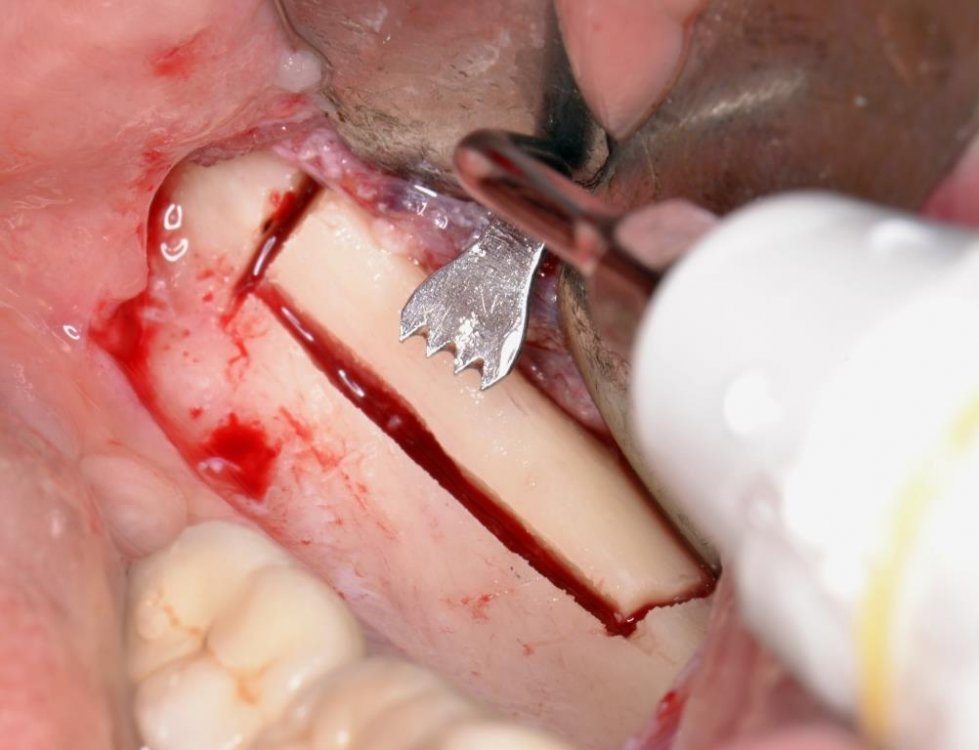

Viene presentato un caso di atrofia ossea passante (c.d. "through-&-through") reliquato di estrazione del 2.4 risolto con una tecnica composita di innesti autologhi in blocco.

post-729-0-89513000-1390144859_thumb.jpg

post-729-0-42358100-1390144877_thumb.jpg

post-729-0-55993300-1390144909_thumb.jpg

post-729-0-53640000-1390144919_thumb.jpg

post-729-0-42078800-1390144943_thumb.jpg

post-729-0-40110700-1390144982_thumb.jpg